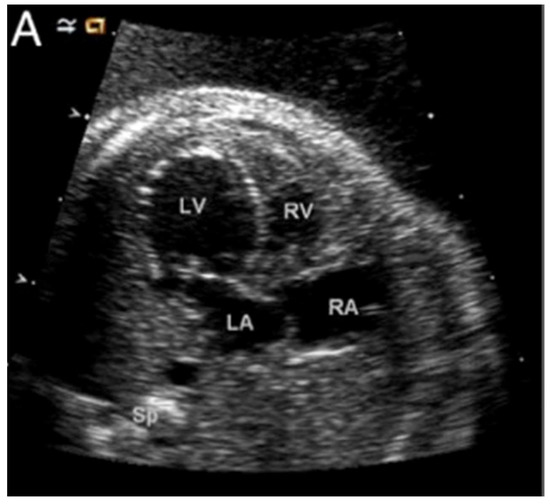

Aortic stenosis is one of the earliest defects to be observed when the hypoplastic left heart syndrome is seen to develop during fetal life [28]. This suggests that, at least in one subset of patients with the syndrome, aortic valvar dysfunction is a prerequisite to the development of the abnormal left ventricle. Figure 7 shows a dilated and poorly functioning left ventricle that is apex-forming at 22 weeks of gestation. With ongoing gestation, this fetus developed the phenotypic findings of the syndrome [28].

Figure 7. A fetal echo of a 22-week fetus with hypoplastic left heart syndrome here shown with a dilated, apex-forming, poorly functioning left ventricle. Abbreviations: LV: left ventricle; RV: right ventricle; LA: left atrium; and RA: right atrium (Reproduced with permission from Feinstein J., et al., JACC, 2011).

The mechanisms leading to the transition from the dilated and poorly function left ventricle to the typical thick-walled ventricle thus far remain unknown. It is intuitive, nonetheless, to suggest that there is initially an arrest in the growth of the left ventricle compared to the right, followed by a thickening of the left ventricular wall. Relevant to this, a potential direct role for the endocardium in the development of the left ventricle was tested by Conway and his associates [29]. They were able to genetically ablate the endocardium during the murine cardiac development. This was achieved by using an endocardial-specific CRE driver to express diphtheria toxin so as to engineer timed and targeted death of the endocardial cells. The perturbation arrested the growth of the left ventricle, resulting in embryonic lethality by E11 (Figure 8). These embryos appear similar to a subset of ETS1 cardiac mesodermal knockdown embryos shown above in that they exhibit growth arrest in the setting of a thin-walled and small left ventricle.